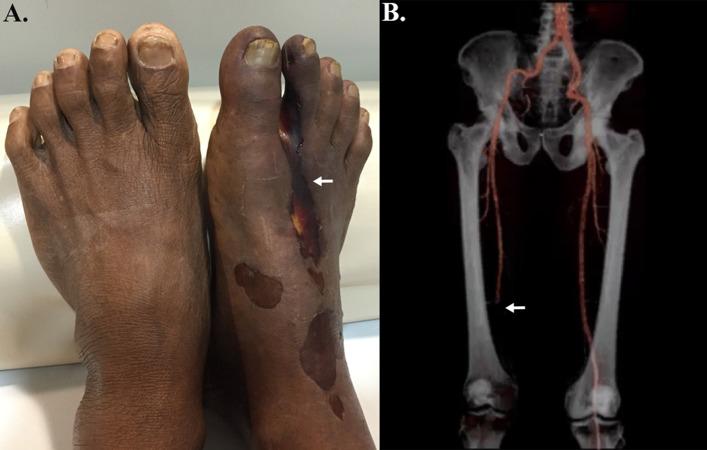

Human pythiosis is an infectious condition with high morbidity and mortality. The causative agent is the oomycete microorganism . The pathogen inhabits ubiquitously in a wet environment, and direct exposure to the pathogen initiates the infection. Most patients with pythiosis require surgical removal of the affected organ, and many patients die from the disease. Awareness of pythiosis among healthcare personnel is increasing. In this review, we summarized and updated information on the diagnosis and treatment of human pythiosis. Vascular and ocular pythiosis are common clinical manifestations. Recognition of the typical clinical features of pythiosis is essential for early diagnosis. The definitive diagnosis of the disease requires laboratory testing, such as microbiological, serological, molecular, and proteomic assays. In vascular pythiosis, surgical intervention to achieve the organism-free margin of the affected tissue, in combination with the use of antifungal drugs and immunotherapy, remains the recommended treatment. Ocular pythiosis is a serious condition and earliest therapeutic penetrating keratoplasty with wide surgical margin is the mainstay treatment. Thorough clinical assessment is essential in all patients to evaluate the treatment response and detect an early sign of the disease recurrence. In conclusion, early diagnosis and proper management are the keys to an optimal outcome of the patients with pythiosis.